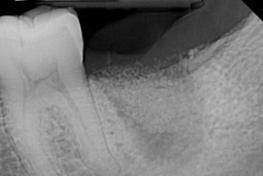

Bone Graft Healed